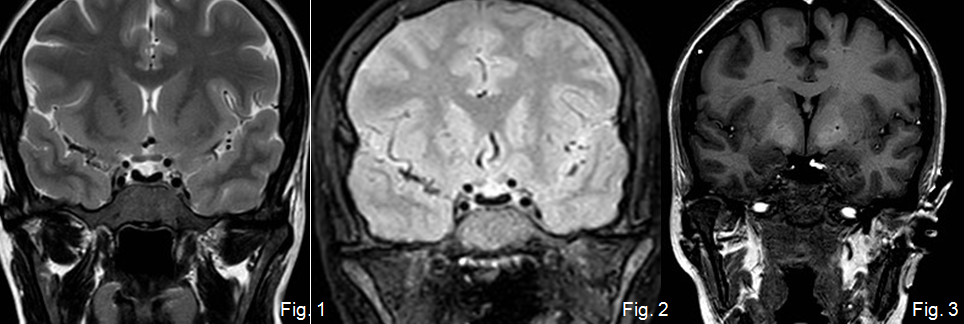

Mujer de 37 años con amenorrea que ingresa por poliuria y polidipsia. Antecedentes de anemia hemolítica no inmune, esplenectomizada. En tratamiento con metformina.

Depósito de hierro en la hipófisis secundario a hemocromatosis secundaria produciendo un hipogonadismo hipogonadotrófico.

La hemocromatosis secundaria es una enfermedad caracterizada por el depósito de hierro en el hígado y en otros órganos. El hierro se puede depositar en la hipófisis, ocasionando un hipogonadismo hipogonadotrofo.

En esta paciente se observa, además del depósito de hierro en la hipófisis, una hiperintensidad de señal de los ganglios basales, hallazgos que pueden ver en la degeneración hepatocerebral adquirida.

Tras la realización de esta RM hipofisaria se le realizaron a la paciente RM de abdomen y de corazón, existiendo también depósito de hierro hepático, pancreático y miocárdico, con diabetes mellitus secundaria.